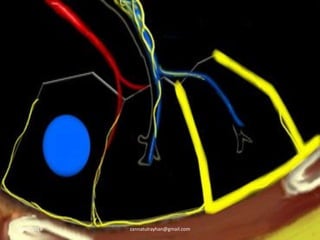

Relevant anatomy

HRCT Interpretation of DPLD is based on the

type of involvement of the secondary lobule.

Secondary lobule:

-smallest lung unit that is surrounded by

connective tissue septa.

-measures about 1-2 cm

-made up of 5-15 pulmonary acini, that

contain the alveoli for gas exchange.

8/27/2019 zannatulrayhan@gmail.com

Contd ..

-supplied by a terminal bronchiole in the center,

accompanying centrilobular artery.

-pulmonary veins and lymphatics run in the

periphery of the lobule within the interlobular septa.

-Two lymphatic systems:

Central network: runs along the bronchovascular

bundle towards the centre of the lobule.

Peripheral network: that is located within the

interlobular septa and along the pleural linings.

Centrilobular area: Central part of the secondary lobule.

-site of diseases that enter the lung through the airways.

ie. hypersensitivity pneumonitis, respiratory bronchiolitis,

centrilobular emphysema.

Perilymphatic area: Peripheral part of secondary lobule.

-site of diseases that are located in the lymphatics / in

interlobular septa.

ie. sarcoid, lymphangitic carcinomatosis, pulmonary edema.